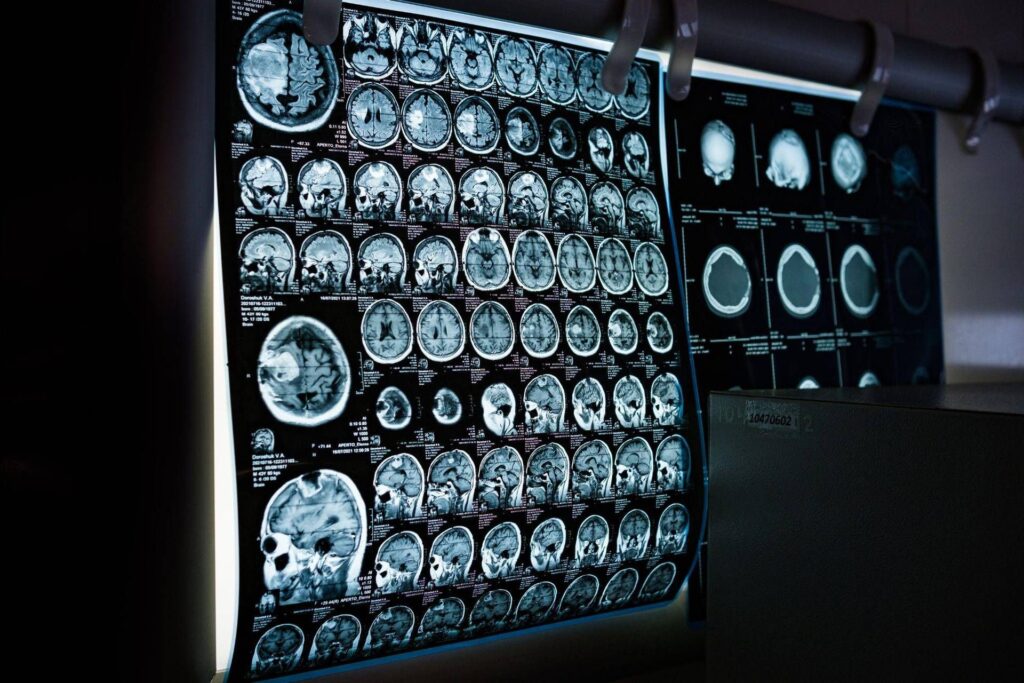

Un spray nasal testé sur des modèles animaux pourrait inverser le vieillissement cérébral avec seulement 2 doses, réduisant considérablement l’inflammation cérébrale, restaurant les centrales cellulaires du cerveau et améliorant ainsi considérablement la mémoire. Un processus de rajeunissement qui agirait d’ici quelques semaines et durerait quelques mois.

C’est le résultat de l’étude menée par des chercheurs de la Texas A&M University (Naresh K. Vashisht College of Medicine) aux États-Unis. Le spray contient de minuscules particules biologiques appelées vésicules extracellulaires (VE), qui agissent comme des véhicules de transport transportant une puissante cargaison génétique, les microARN. Les substances contournent le bouclier protecteur du cerveau et voyagent directement dans les tissus cérébraux, où elles sont absorbées. Arrivés à destination dans les cellules immunitaires résidant dans le cerveau, les microARN « désactivent » les systèmes connus pour être responsables de l’inflammation chronique du cerveau vieillissant.

Pour expliquer le sens de ce processus, les scientifiques nous invitent à imaginer le cerveau comme un moteur performant : au fil des décennies, ce moteur non seulement s’use, mais commence également à surchauffer. De petits « foyers » d’inflammation couvent au plus profond du centre de la mémoire, créant un brouillard cérébral persistant qui rend plus difficile la réflexion, la formation de nouveaux souvenirs ou même l’adaptation à de nouveaux environnements, tout en augmentant le risque de troubles tels que la maladie d’Alzheimer. Ce processus à combustion lente est appelé neuroinflammation. Et pendant des décennies, on a pensé que c’était le prix inévitable du vieillissement. Mais la nouvelle étude, publiée dans le « Journal of Extracellulaire Vesicles », suggère que la vague inflammatoire pourrait être réversible.

L’équipe dirigée par Ashok Shetty, professeur distingué de l’université et directeur associé de l’Institut de médecine régénérative, en collaboration avec les chercheurs principaux Madhu Leelavathi Narayana et Maheedhar Kodali, a développé le spray nasal et vérifié qu’au niveau cellulaire, le traitement rechargeait les mitochondries neuronales, c’est-à-dire les plantes énergétiques présentes à l’intérieur des cellules cérébrales. La thérapie a dissipé le brouillard mental et a également amélioré physiquement la capacité du cerveau à traiter et à stocker les informations.

« Nous redonnons de la vitalité aux neurones en réduisant le stress oxydatif et en réactivant les mitochondries du cerveau », souligne Narayana. Dans les modèles traités, les tests comportementaux ont confirmé les résultats biologiques, montrant des améliorations notables non seulement dans la reconnaissance d’objets familiers, mais aussi dans l’identification de nouveaux objets et de changements dans l’environnement, en contraste frappant avec le groupe témoin.

« Les maladies liées au vieillissement cérébral, comme la démence, représentent un grave problème de santé mondial – souligne Shetty – Ce que nous démontrons, c’est que le vieillissement cérébral peut être inversé, en aidant les gens à garder l’esprit vif, à rester socialement actifs et à ne pas souffrir de déclin cognitif lié à l’âge ». L’étude suggère une large applicabilité du spray. Les résultats du traitement, explique Shetty, « étaient cohérents et similaires chez les deux sexes ». Le mode d’administration « est l’un des aspects les plus intéressants de notre approche », commente Kodali. « L’administration intranasale nous permet d’atteindre et de traiter directement le cerveau, sans recourir à des procédures invasives. »

Quant aux effets, ce qui est observé, c’est « l’activation des systèmes de réparation du cerveau, qui guérissent l’inflammation et se régénèrent », suggère Shetty. Des recherches supplémentaires sont évidemment nécessaires pour confirmer ces résultats, mais Shetty et son équipe ont déjà déposé un brevet américain pour cette thérapie. Les travaux ont été réalisés avec le soutien de l’Institut national du vieillissement (Nia).